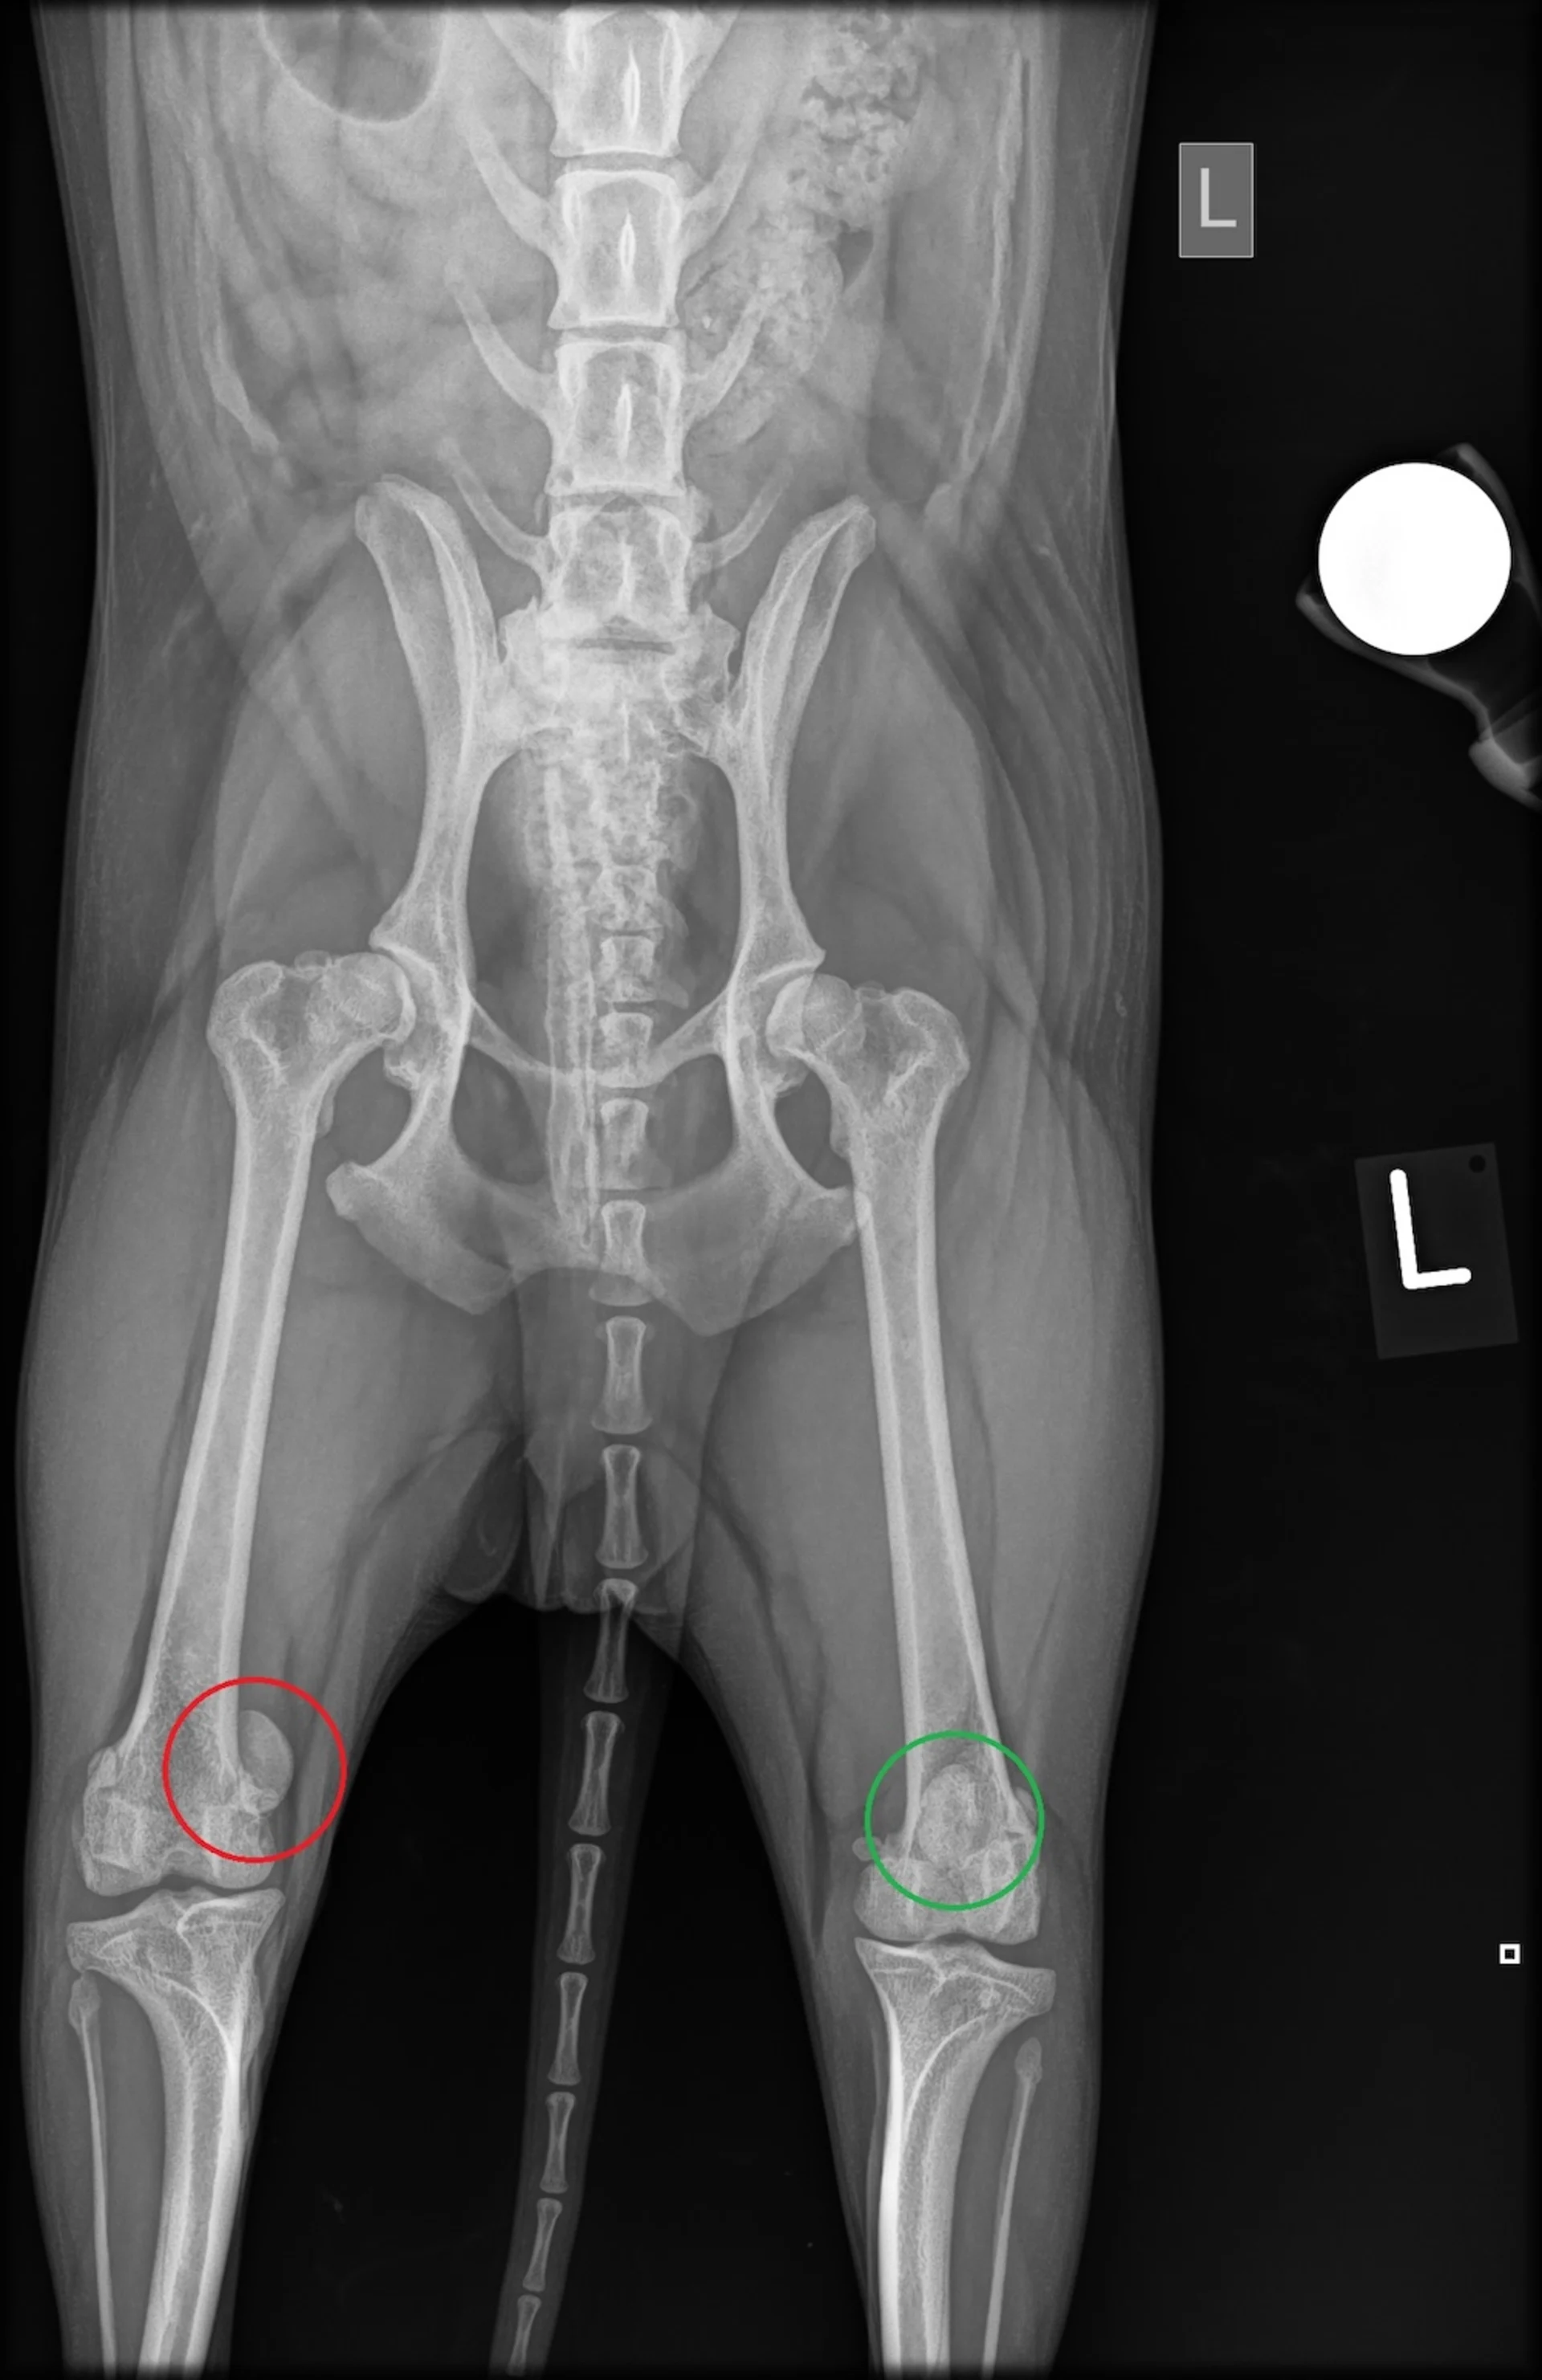

Radiographie